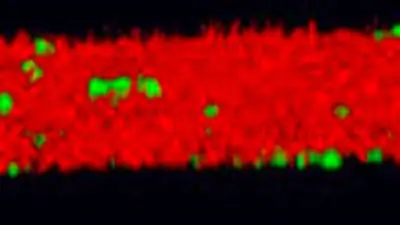

Caption: In the presence of the inhibitor, P. gingivalis (green) is prevented from adhering to S. gordonii (red) and biofilm production is significantly reduced.